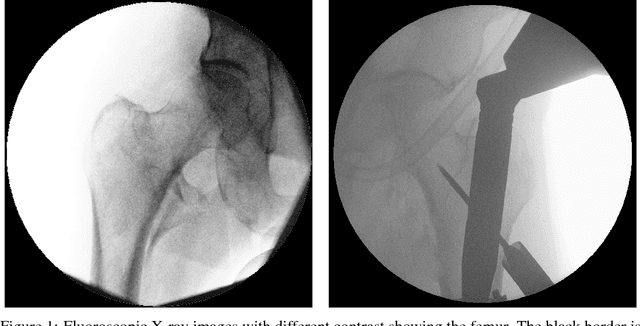

Abstract:We propose approaches based on deep learning to localize objects in images when only a small training dataset is available and the images have low quality. That applies to many problems in medical image processing, and in particular to the analysis of fluoroscopic (low-dose) X-ray images, where the images have low contrast. We solve the problem by incorporating high-level information about the objects, which could be a simple geometrical model, like a circular outline, or a more complex statistical model. A simple geometrical representation can sufficiently describe some objects and only requires minimal labeling. Statistical shape models can be used to represent more complex objects. We propose computationally efficient two-stage approaches, which we call deep morphing, for both representations by fitting the representation to the output of a deep segmentation network.